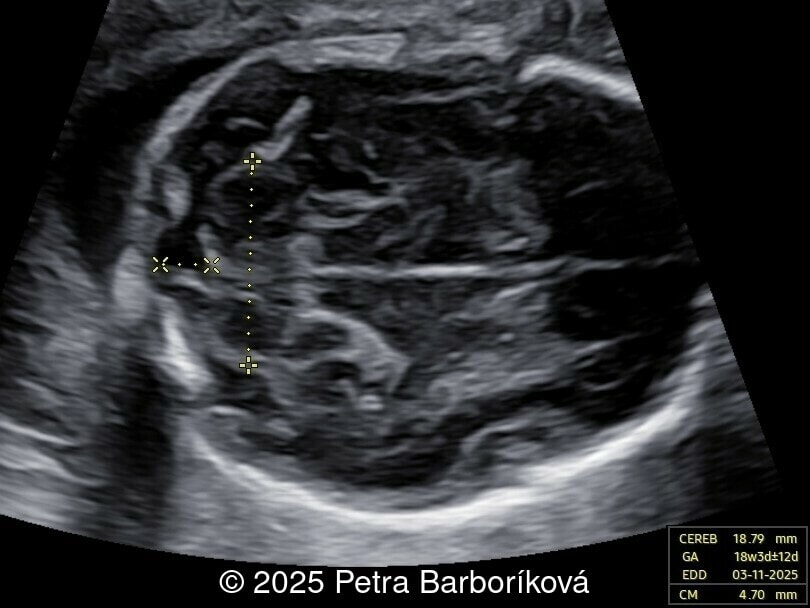

A 26-year-old primigravida with no significant past medical or family history was admitted at 18 weeks of gestation with preterm premature rupture of membranes. At 20 weeks of gestation, a detailed fetal ultrasound was performed under conditions of severe oligohydramnios, followed by fetal magnetic resonance imaging (MRI). Non-invasive prenatal testing (NIPT) for common aneuploidies was negative.

At 20 weeks, detailed ultrasound under conditions of severe oligohydramnios demonstrated absence of the typical box-shaped anechoic structure of the cavum septum pellucidum (CSP). The frontal horns of the lateral ventricles appeared narrow and pointed, giving the characteristic “bull’s horns sign.” Multiplanar and 3D reconstructions confirmed the presence of the corpus callosum, while the CSP was absent. Other midline and posterior fossa structures appeared normal. The optic chiasm was partially visualized, although assessment was limited by technical conditions. Fetal magnetic resonance imaging (MRI) was subsequently performed and confirmed isolated agenesis of the CSP with preserved corpus callosum and posterior fossa structures. The optic chiasm and pituitary stalk are visible in the sellar region, but the pituitary gland itself is not clearly identified in the sella turcica as it is a very small structure. No additional central nervous system anomalies were detected.